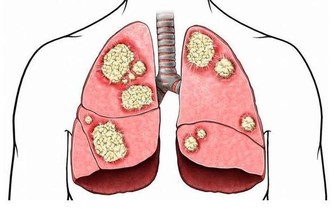

英國科學癌症研究中心研究了世界各地1000餘名30歲-50歲的癌症患者,

發現99.3%的人常年熬夜,凌晨後才會休息。

熬夜一方面會造成生物鐘紊亂,另一方面,夜間燈光會破壞人體褪黑素形成,

而這是保護人體免疫功能的重要一環,缺少它容易讓白血病、乳腺癌、前列腺癌等找上門來。

此外,長期睡眠不足還容易引發高血壓、心\臟病、中風、肥胖和其他健康問題。